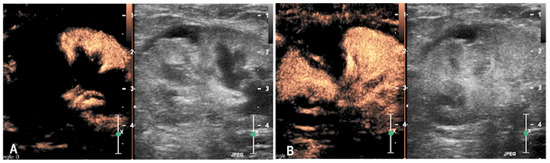

3.2. Case 2